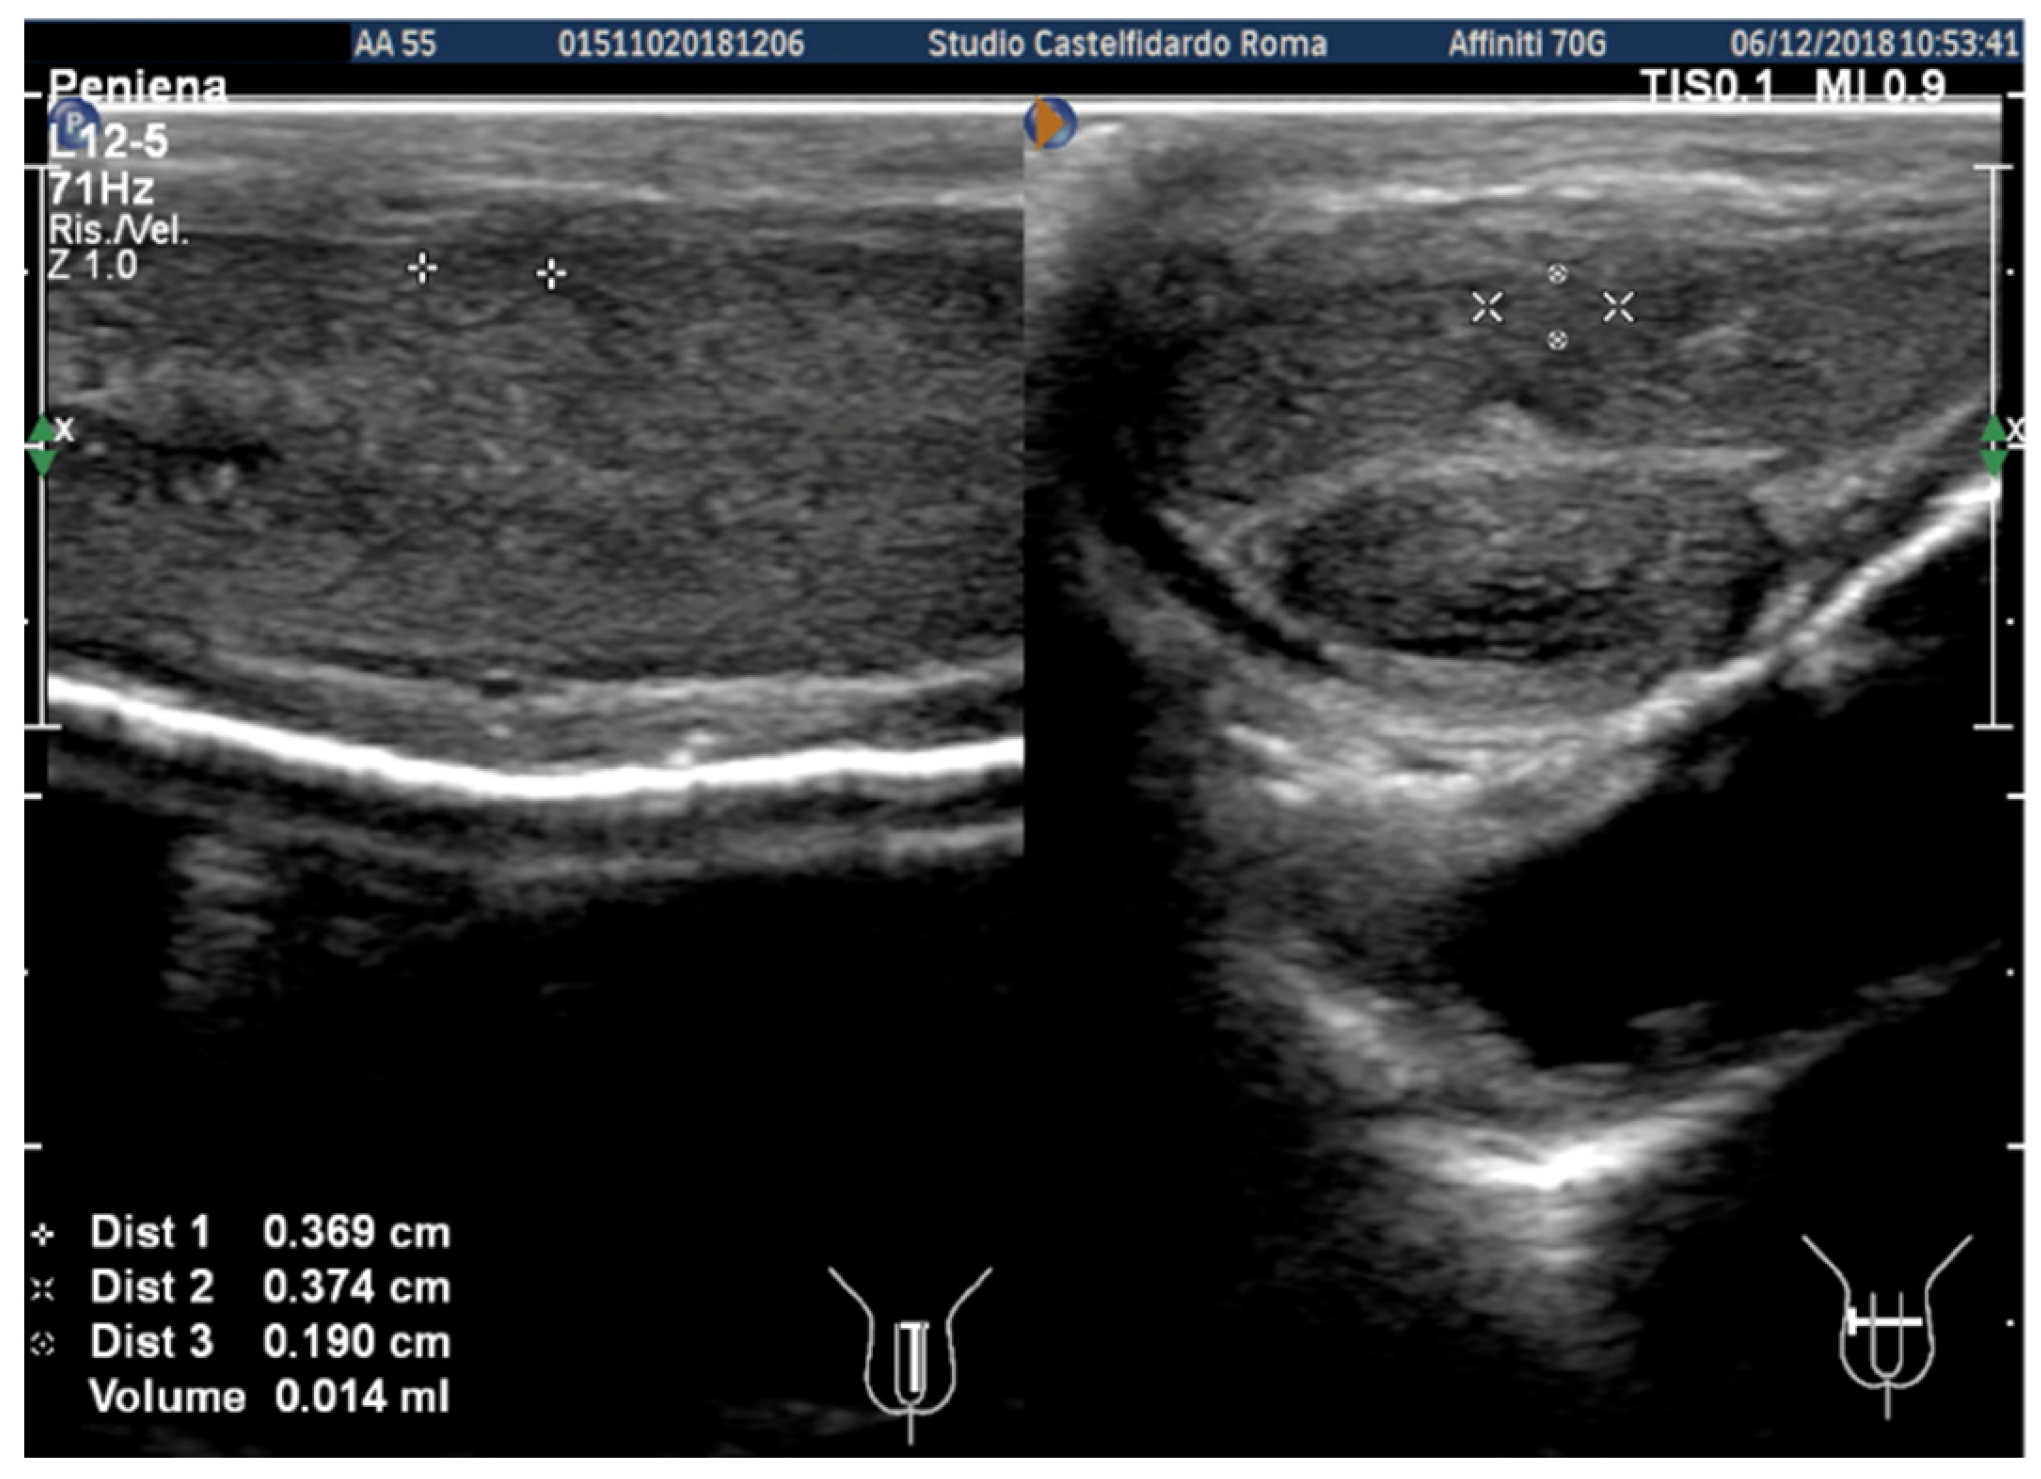

| 1 | 31 years | Chronic prostatitis and associated anxious and depressive state. | Distal third | (A) 15.1 × 12.1 × 3.7 mm volume = 353 mm3 (B) No plaque detected | (A) 10-degree ventral curvature + 15-degree left curvature (B) None | VAS score = 8 Pain disappeared after 12 months | 26 > 27 | 30 months | Orally: propolis 600 mg + bilberry 160 mg + silymarin 400 mg + ginkgo biloba 250 mg + L-carnitine 1000 mg + coenzyme Q10 100 mg + Boswellia 200 mg + Vitamin E 30 mg/daily/for 30 months + topically: diclofenac gel 4%/2× daily for 30 months Note: The patient refused periplaque penile injections with pentoxifylline |